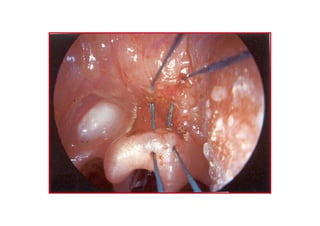

ARAR TENOTENO DEKTOMDEKTOM

ENDOSKOPENDOSKOP KK

ThornellThornell

COCO22 laserlaser

ENDOSKOPENDOSKOP K LASERK LASER

SubmukozalSubmukozal

eksizyoneksizyon

krutkrut,, grangranüülasyonlasyon,,skarskar ØØ